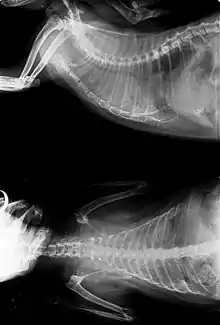

X-ray of FeLV-positive cat with lung cancer

• X-rays may or may not make use of contrast techniques to help visualize the gastrointestinal tract. They are commonly used to identify tumors of the lung, gastrointestinal tract and bladder.